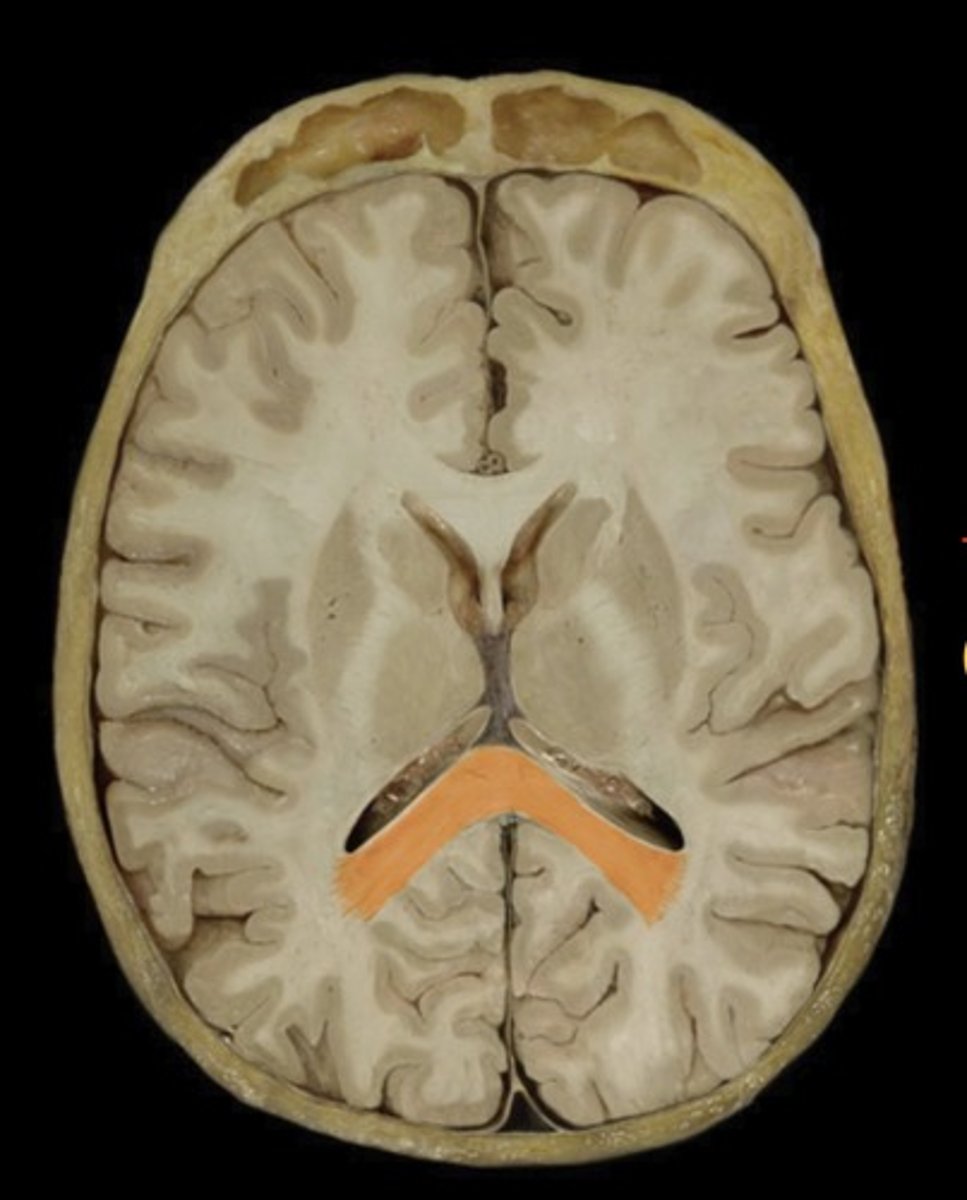

Posterior Horn of the lateral ventricle

Name this structure

Splenium of corpus callosum

Name this structure

Temporal Lobe (transverse section)

Name this structure

Thalamus (transverse section)

Name this structure

Gray matter

Name this structure

White matter

Name this structure

Cerebrum

Name this structure

Longitudinal fissure

Name this structure